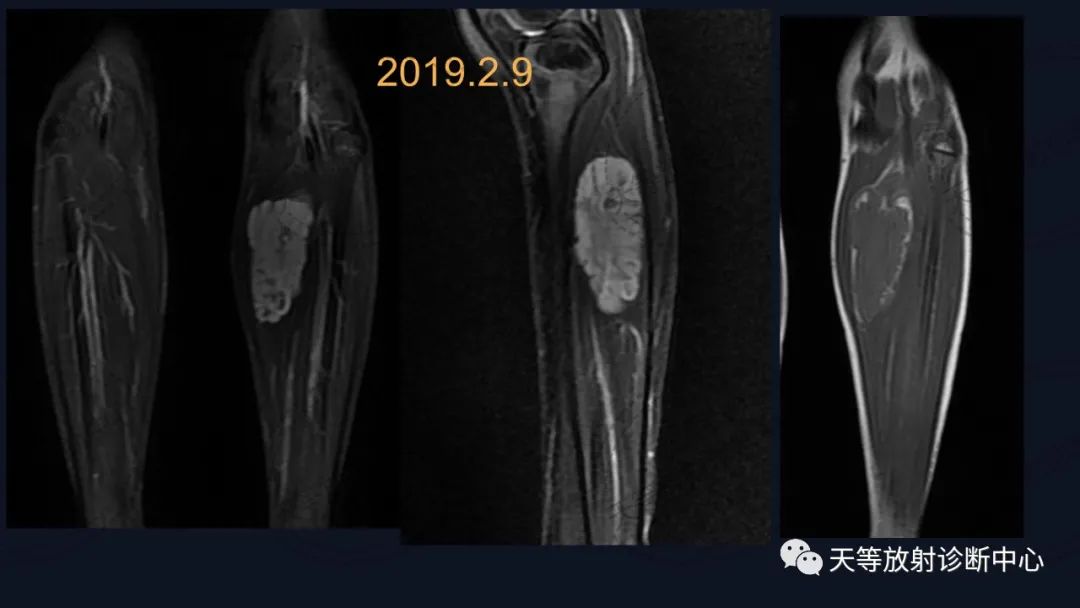

病例,儿童男性

上图:压脂序列肿块椭圆形,内部见细小分隔,血管流空信号。

T1WI肿块边缘见环状高信号影,考虑出血信号。

前后两次对比观察,病灶略有增大。